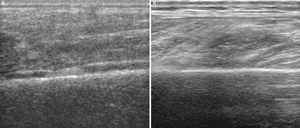

Utilizando el equipo E-A, en un corte longitudinal sobre el músculo gemelo externo a la altura del tercio superior (fig. 2A) se observa la referencia ósea que corresponde a la cortical del peroné, y en un plano superior no se aprecia discontinuidad focal de las fibras ni la presencia de un hematoma intramuscular, debido posiblemente al prolongado tiempo de evolución (1 mes). Por el contrario, con E-B se aprecia una zona hipoecoica en el vientre muscular del gemelo externo (fig. 2B), de aspecto irregular y lineal no visualizable con el E-A, lo cual facilita la confirmación ecográfica de la sospecha clínica.

Figura 2 A) Aspecto fibrilar normal en un corte longitudinal del músculo gastrocnemio externo sobre el peroné en una imagen de E-A. B) En un corte longitudinal con E-B se observa el área hipoecoica en el vientre del gemelo externo.